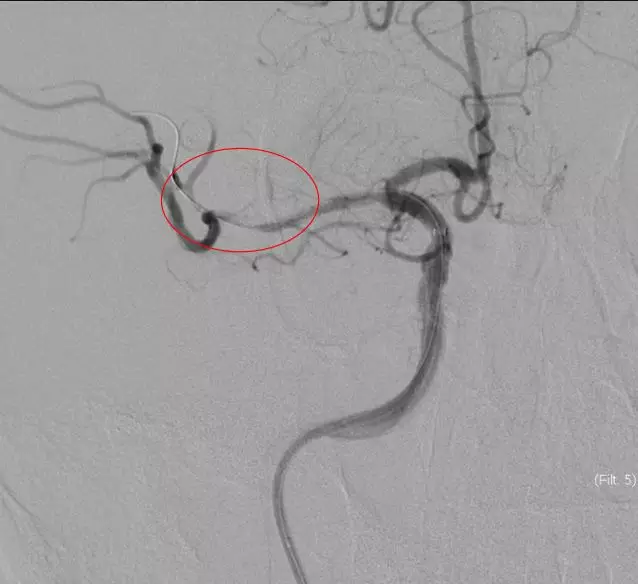

立即DSA(08-03日 13:24分)

5MIN后